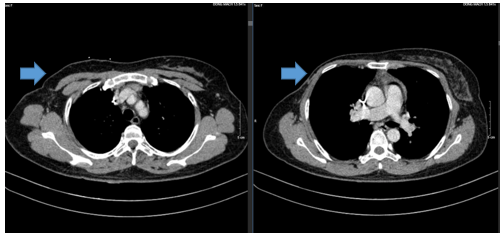

- MRI vú trước điều trị:

Hình 1:

Vú phải vị trí 1/4 dưới ngoài, cách núm vú 15mm có khối ~ 70x59x37mm, tổn thương xâm lấn da (đường kính 34mm. Nằm sát khối lớn, vị trí trung tâm ngoài, cách núm vú 13mm có nốt 7x10mm, ngấm thuốc mạnh ở pha sớm. Hố nách bên phải có vài hạch thuộc chặng 1 ~9x14mm, còn rốn hạch, hạch thuộc chặng 2 ~5mm, ngấm thuốc mạnh sau tiêm.